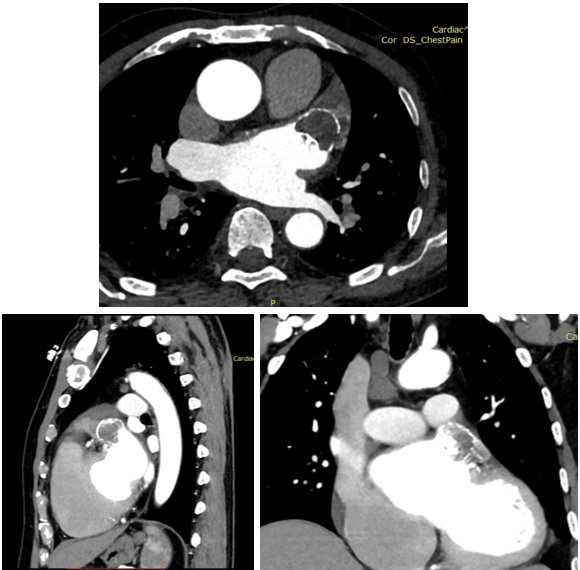

左心耳ct增强

左心耳ct三维重建:评估指南与注意事项